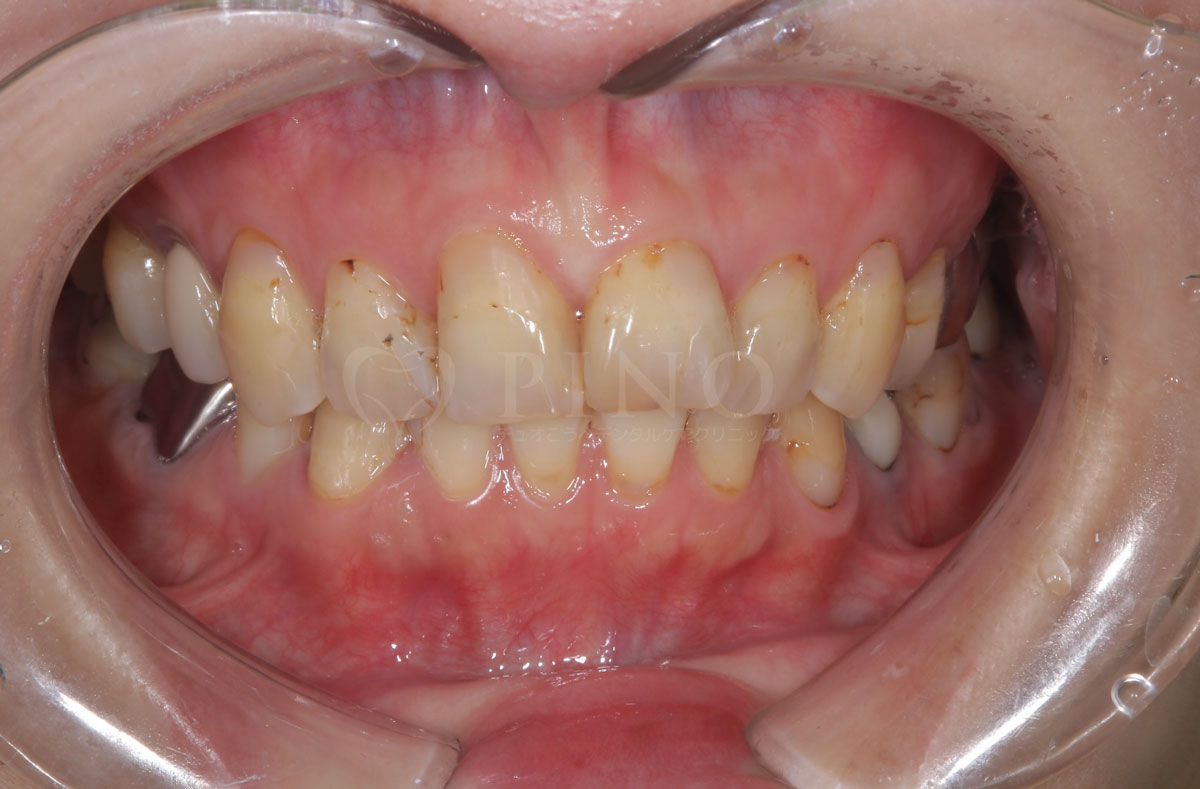

症例12:噛み合わせが深く、下の歯が見えないのが気になる(20代男性)

主訴 噛み合わせが深く、下の歯が見えないのが気になる 診断名 過蓋咬合(かがいこうごう)、顎関節後方転位 治療方法 マウスピース矯正、補綴治療(被せ物、詰め物の治療) 抜歯 なし オルソパルス あり 治療期間 2年 費用 746,000円 + 165,000円(オルソパルス)+ 補綴費用(保険診療) 副作用・注意点 矯正後の後戻りを防ぐためリテーナーの使用が必要となる、詰め物の変色が起こる可能性がある 備考 下顎の位置を正しい位置にするためにスプリントを使用した。ホワイトニングも併用。